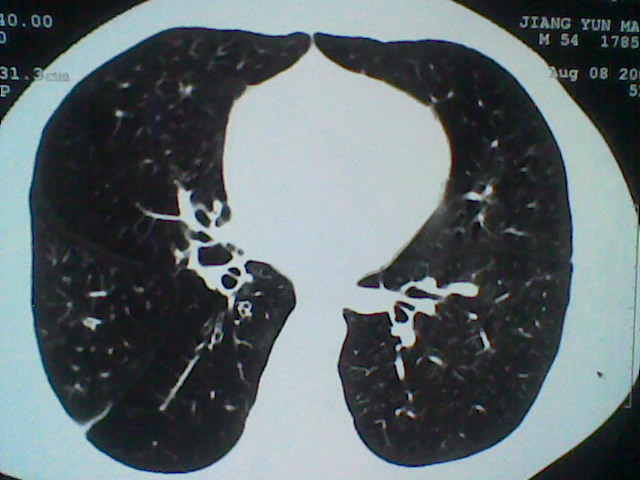

标题: CT21512:支扩伴感染?

患者女。咳嗽数天,咯血半天。

我们报的是支扩伴感染?

支持 支气管扩张并感染。

支持楼主意见,考虑支气管扩张并感染。

支气管扩张并感染。

支持楼主意见,还有肺气肿